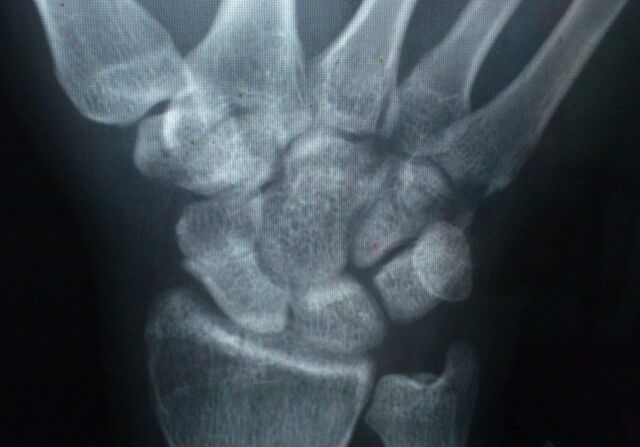

明天脊柱科会诊一个腰椎骨折合并舟骨骨折患者

有几个月没有做舟骨骨折了

舟骨位于腕骨近排,是近排腕骨和远排腕骨间的铰链

是腕骨骨折的最常见部位

Herbert分型:急性稳定型、急性不稳定型、延迟愈合及骨不连

解剖学上分为:近极,腰部,远极

舟骨和桡骨、月骨、头状骨、大多角骨、小多角骨向关节

舟骨表面几乎为透明软骨覆盖,没有骨膜,血供差

舟骨骨折的愈合为一期愈合,愈合过程中没有骨痂形成

在愈合早期生物力学强度差

舟骨腰部骨折后骨不连的发生率为5%-10%